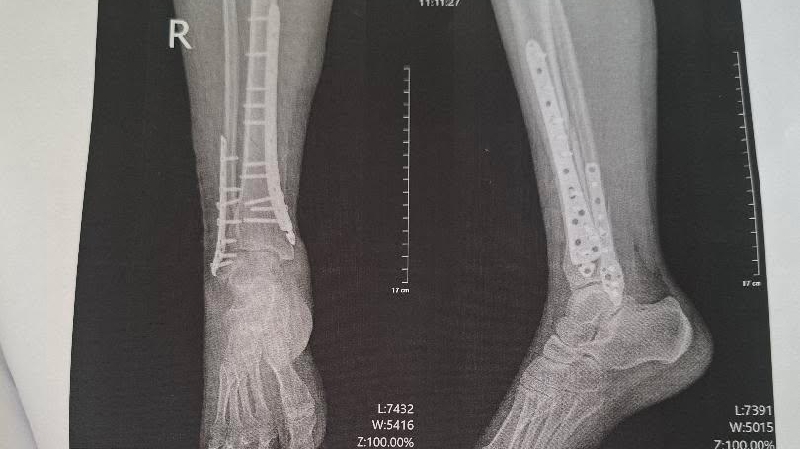

The sad part is, I was trying to get her out of danger. So she wouldn’t be hurt, or worse. On January 2nd, while walking her dog, she slipped on the ice and broke her lower leg. Both Tibia and Fibula.She went through an emergency surgery to immobilize her leg and eventually had plates put in to stabilize the bones. I am not sure if you are familiar with the Ukrainian healthcare system, but she went through all of this without pain medication. With my medical background, I was asking what medications she was taking. She told me benadryl for sleep and an NSAID for pain. All of which she had to pay for out of pocket.

The surgery and hospital stay would have cost over $40,000 here in the United States. But, she informed me it is about $2,000 for her in Ukraine. After 3 weeks in a hospital bed, Nataliia was finally discharged from the hospital, without a cast, wheelchair, crutches, or medication. She was told to stay off of it for 3 months and showed how to bandage the surgical wounds. I am not sure when she will be able to work.